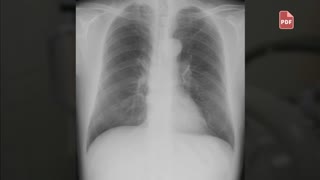

63歳の男性(前胸部痛)。72歳の男性(突然の背部痛と冷汗)。78歳の男性(呼吸困難と下腿浮腫)の3症例を収録しています。